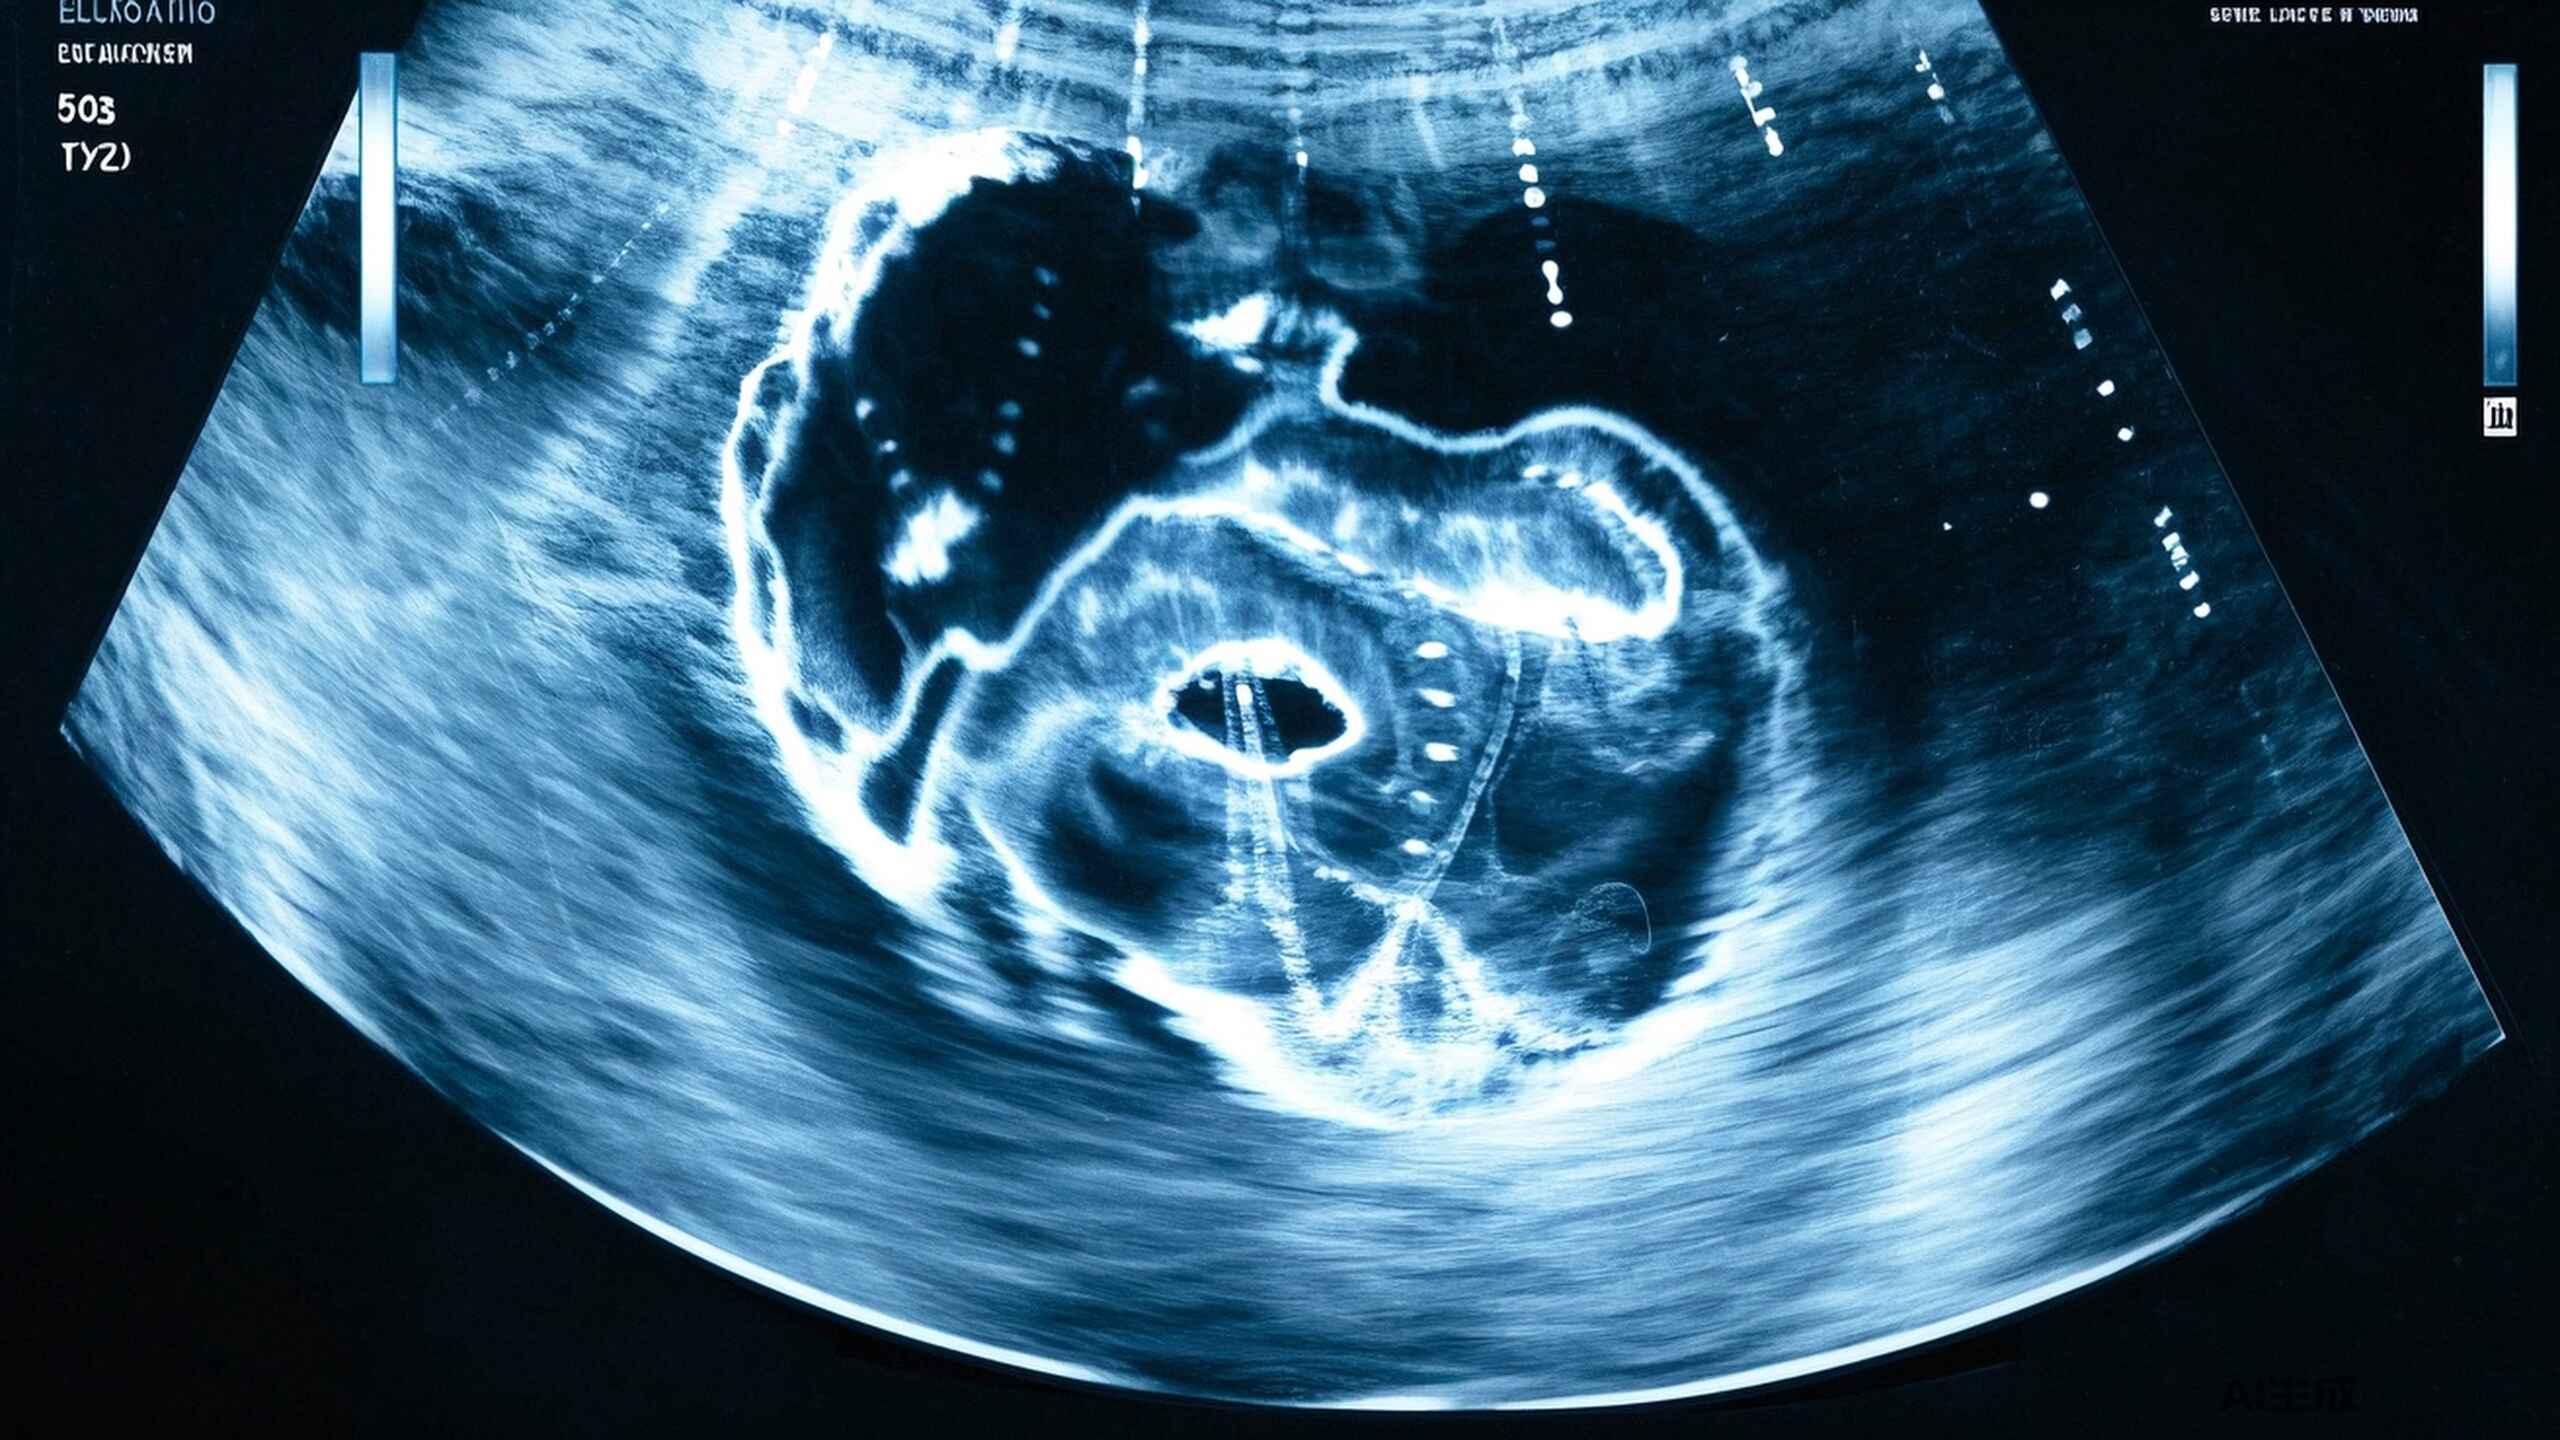

胆囊炎的超声表现:不止是“胆”那么简单

本文深入探讨胆囊炎的概述、超声成像原理、急性与慢性胆囊炎的超声特征、合并症表现及预防措施,为患者和医务工作者提供全面的胆囊健康指导。